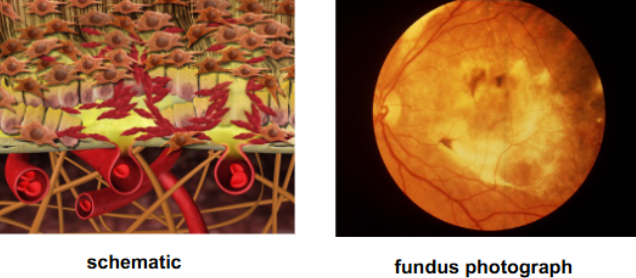

characterized by development of macular neovascularization which leak & bleed into surrounding tissue ultimately leaving a fibrovascular scar or disciform scar

ingrowth of new vessels extending from the choroid into sub-RPE space in one or more areas

neovascular buds invade & penetrate the degenerated Bruch’s membrane & proliferate beneath the RPE

new vessels grow into & break through Bruch’s

new vessels continue to grow under RPE

drusen are resorbed

new vessels continue to grow under RPE

exudation due to vessels leaking fluid into sub-RPE space

fluid breaks into sub-retinal space through RPE

type 2 CNV develops which may show classic components or remain occult to FA depending on RPE cells’ migration to envelop the membrane

describe the development of wet AMD